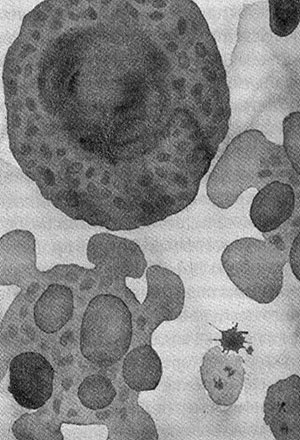

Когда клетки тела изнашиваются или повреждаются, они погибают в результате насильственного самоубийства — апоптоза. Клетка распадается на части, они упаковываются и перевариваются. Нарушение механизмов апоптоза приводит к раку — конфликту интересов отдельных клеток и организма в целом. Видимо, апоптоз необходим для обеспечения целостности многоклеточных организмов, но почему независимые клетки согласились на гибель ради высшего блага? Сегодня апоптоз контролируется митохондриями, которые унаследовали машину смерти от своих предков-бактерий. Так неужели целостность индивидуума действительно родилась в борьбе не на жизнь, а на смерть?

Иллюстрация к книге — Энергия, секс, самоубийство. Митохондрии и смысл жизни [i_019.jpg]

Смерть от апоптоза: жить клетке или погибнуть, решают митохондрии